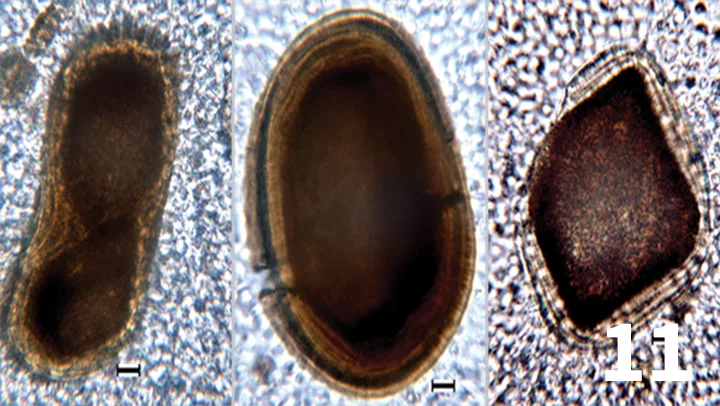

Unstained urine wet mount, 50× objective, bar = 10 µm. Photomicrographs showing crystalline structures that were numerous in the urine sediment. The crystals are dark brown, variably shaped, and exhibit a concentric layering effect. Courtesy of Diagnostic Cytology and Hematology of the Dog and Cat, Valenciano AC, Cowell RL (eds).

A 15-year-old castrated Jack Russell terrier was presented with seizures that were refractory to medical management. During hospitalization, medications included zonisamide, levetiracetam, dexamethasone, acetylcysteine, furosemide, and mannitol. As part of the diagnostic evaluation of neurologic disease, a urinalysis was performed. Photo-micrographs of the urine sediment are shown in Figure 11.

The patient’s refractory seizures were associated with an intracranial mass. The polypharmacy used to treat this patient was likely the cause of the crystals. A number of drugs have been associated with crystalluria in human and veterinary patients. Anticonvulsant polypharmacy has specifically been studied in the human literature. Patients receiving zonisamide, a sulfa-containing medication, and patients taking multiple medications frequently had crystalluria.7

- No, the crystals are unusual.

- The crystals are likely formed from precipitated drugs or drug metabolites, given the patient was on multiagent therapy that included anticonvulsant drugs.